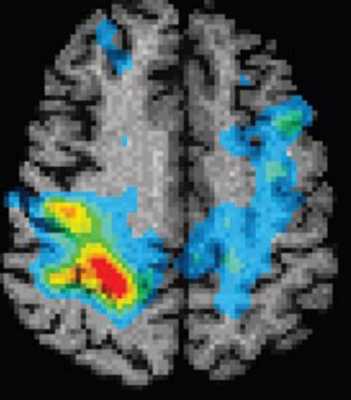

Роль МРТ в диагностике эпилепсии

МРТ головного мозга. Функциональный метод. Эпилептогенный очаг. Цветовая обработка изоборажения.

Эпилепсия - это повышенная электрическая активность мозга. Участок возбуждения в коре головного мозга, в зависимости от того, в каком месте он находится, приводит к различным клиническим проявлениям. Наиболее широко известны судорожные припадки, хотя эпилепсия не обязательно судороги.

МРТ играет выжную роль в установлении причины эпилепсии, в первую очередь в исключении опухоли.

Особый случай представляет собой эпилепсия, когда припадки сопровождаются потерей сознание. Такой вариант эпилепсии (парциальная комплексная эпилепсия) связан с поражением височной доли мозга. МРТ головного мозга позволяет увидеть уменьшение объёма участка височной доли (“склероз медиального отдела височной доли”). Это чрезвычайно важно, так как по нашим данным МРТ в СПб нейрохирурги могут удалить повреждённый участок и эпилептические припадки прекратятся.